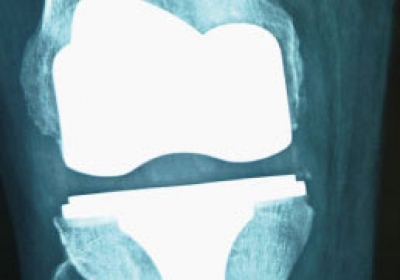

CIRUGÍA PROTÉSICA, MIS Y DE RECAMBIO

En aquellos casos en los que la articulación está deteriorada y los tratamientos conservadores no quirúrgicos no mejoran el dolor e incapacidad funcional del paciente es cuando está indicado un reemplazo articular.

Este reemplazo (artrosplatias) pueden ser unicompartimentales o totales según la extensión del desgate del cartílago, llegando a realizar miniartoplastias en aquellos casos en los que la zona a sustituir de la articulación es muy limitada.

Prótesis en gente joven

La indicación de la prótesis se basa en el grado de afectación , limitación funcional y el dolor; y secundariamente en la edad, por lo que en ocasiones, puede ser necesaria una cirugía protésica en gente joven, como por ejemplo en la artritis reumatoide juvenil o en lesiones post.traumaticas graves. En estas ocasiones es recomendable utilizar diseños que aseguren la máxima durabilidad del implante como es el caso de las prótesis rotatorias o de platillos móviles u otros como el de la Protesis Advance Medial Pivot (Wrigth), que imita la funcionabilidad de la rodilla humana.¿Qué es la cirugía MIS (Minimal Invasive Surgery)?

Este tipo de cirugía consiste en practicar la implantación de prótesis mediante incisiones muy pequeñas que respetan al máximo las partes blandas. De esta forma, conseguimos acelerar la recuperación y reducir el tiempo en la clínica del paciente, que sólo está unos pocos días. Siempre en aquellos casos en los que este indicado. Siempre valorando cada caso en particular para poder garantizar los mejores resultados y sin olvidar el principal objetivo: asegurar un resultado que perdure en el tiempo.Sustitución de prótesis: recambios y revisiones

Especial atención y dedicación requiere los tratamientos de aquellas prótesis dolorosas que muchas veces requieren ser retiradas y sustituidas por otras. Son casos delicados, que exigen serios protocolos tanto en el diagnóstico del problema como en la implantación de la nueva prótesis.